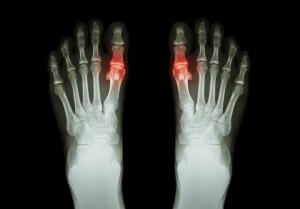

痛風は、関節内に微結晶または尿酸が蓄積することによって生じる症状です。結晶は皮膚の下に膨らみを形成したり、尿路に沈着します。

しかし、これがうまくいかないと、尿酸値が異常に上昇します。結晶が形成されて関節内に沈着し、鋭い痛みを感じるようになります。

- 初めのうちは、1つもしくは数カ所のみの関節だけが痛みを感じます。一般的に、膝や足首、親指に痛みを感じます。痛みは数日中になくなるケースが多いですが、またしばらくすると出てくることもあります。

- 通常、痛風に侵された関節は、熱くて赤いです(炎症を起こしています)。非常に敏感で腫れやすい傾向があります。